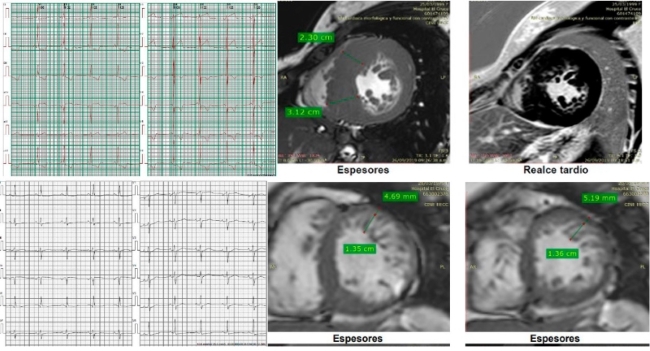

The index case is a woman with severe

hypertrophy diagnosed at the age of 37, with ICD implantation for syncopal sustained monomorphic ventricular tachycardia (VT)

at the age of 47. The CMR showed non-compacted myocardium (NCM) and G+ (MYH7:

c.1208G>A (p. Arg403Gln). Her 3 sons have G+, two of them with F+,

pathological ECG (left ventricular hypertrophy and negative T waves on the

anterolateral side). Above: ECG and CMR of one of her sons. Below: patient's

ECG and CMR.